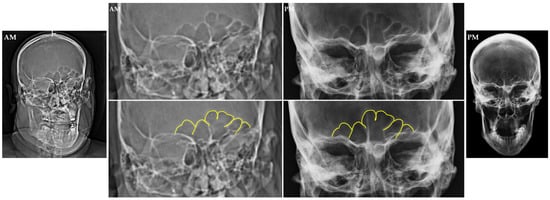

Since the first clinical use of computed tomography in 1971, its clinical application increased rapidly through the 1980s until the 2000s, when CT techniques became a key component of modern radiology [29,30,31,32]. Due to the extended use of the CT-scans in the clinical context, cranial CTs are frequently provided as antemortem medical records, which can be compared to postmortem imaging, which in most cases consists of radiography. Although CT scans contain volumetric data, and despite the current extensive research in three-dimensional comparison and overlay of the paranasal sinuses, 3D renderings of the sinuses aren’t generally of great use in forensic identification daily casework, since most of the comparisons are conducted between an antemortem CT scan and a postmortem radiograph, given the accessibility to this technique in the forensic institutions. According to that, forensic practitioners often use reformatting tools rather than using 3D reconstructions, which do not offer information on the internal structure of the sinuses (Figure 3).

Figure 3. Antemortem (AM) 3D rendering reconstruction from a CBCT scan (a); postmortem (PM) anterior posterior cranial radiograph (b); volumetric reconstruction of frontal sinus in AM CBCT scan (c). The frontal sinus outline and septa are highlighted in yellow in the lower images. The cut in the CBCT in (a) was conducted at a level that allows the visualization of the overall sinus, thus can be compared with the postmortem radiograph (b), while the volumetric reconstruction (c) lacks the ultrastructure information visible in the postmortem radiograph. Source: Department of Applied Forensic Sciences at Mercyhurst University casework.